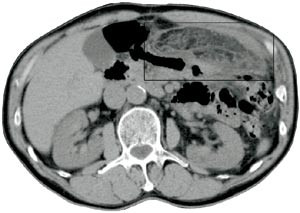

Pasient 2. En 42 år gammel mann, tidligere appendektomert og operert for etterfølgende adheranseileus, kom inn med konstante smerter i høyre nedre kvadrant av halvannet døgns varighet. Han hadde redusert matlyst, men ikke oppkast. Ved klinisk undersøkelse var han subfebril og hadde en palpabel oppfylling til høyre for umbilicus og tegn til peritonitt. Ultrasonografi viste, svarende til palpasjonsfunnet, en ekkorik, relativt homogen oppfylling med et par små sentrale hypoekkoiske foci. Den var velavgrenset fra tarm, 3 x 8 cm stor og med litt ødem omkring (fig 3). CT fremstilte i samme lokalisasjon en skarpt avgrenset lavattenuerende, inhomogen oval oppfylling med omliggende ødem. Den var 10 x 4 cm stor og hadde utseende som ødematøst fettvev (fig 4). Røntgen thorax og oversikt abdomen var upåfallende. Preoperativ diagnose var uspesifisert oppfylling eller infiltrat, sannsynligvis uten relasjon til tarm. Pasienten ble laparotomert, og det ble funnet torsjon av en del av omentet, med begynnende nekrose. Affisert fettvev ble fjernet og diagnosen verifisert ved histologisk undersøkelse.

Ultrasonografisk viser lesjonen seg som en rund eller oval ekkorik oppfylling lokalisert til ømhetens punctum maximum (1, 6) – (8). Oppfyllingen er ikke-komprimerbar og ofte adherent til peritoneum, sistnevnte demonstreres best i sagittalplan, hvor man under respirasjon kan observere lesjonens manglende bevegelighet i forhold til øvrig intraperitonealt innhold (7). Det ses ofte et 1 – 2 mm tynt, hypoekkoisk sjikt rundt oppfyllingen. Andre beskrevne assosierte funn er hypoekkoiske foci inni lesjonen som sannsynligvis representerer hemoragiske forandringer, fortykkelse av tilgrensende tarmvegg og peritoneum og masseeffekt med dislokasjon av tarm. Ved bruk av fargedoppler ses manglende blodstrøm.